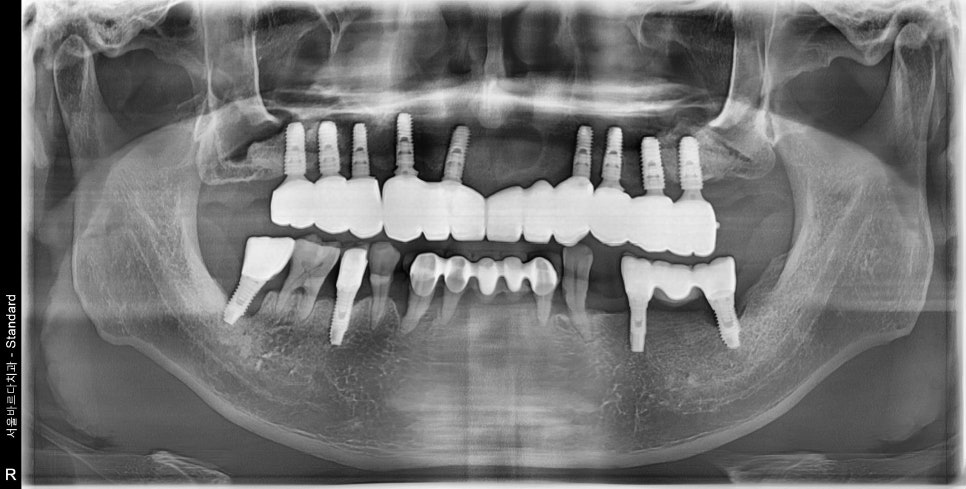

식립 후 사진입니다.

231129

눈썰미 좋은 신 분은 벌써 달라진 점을

눈치채셨을 텐데요.

식립 전

식립 후

식립 전에는 이 하얀 부분인 뼈가 굉장히 얇았는데,

식립 후에는 이 하얀 부분이 더 많아진 것을 볼 수 있어요.

이 하얀 부분이 바로 뼈이식을 한 부위입니다.

임플란트 식립한 각도나 위치 모두 제가 원하던 위치에 심어졌습니다.

240108